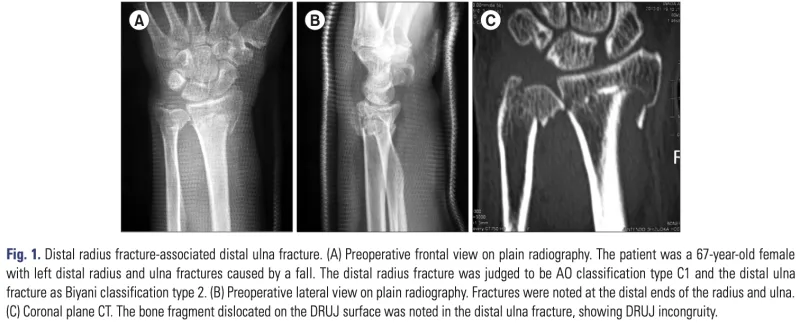

X線撮影の結果, 上腕骨頚部骨折と前腕骨(橈骨・尺骨)遠位端骨折を確認.

橈骨は骨折部で短縮, 尺骨は骨折部で回転してズレています.